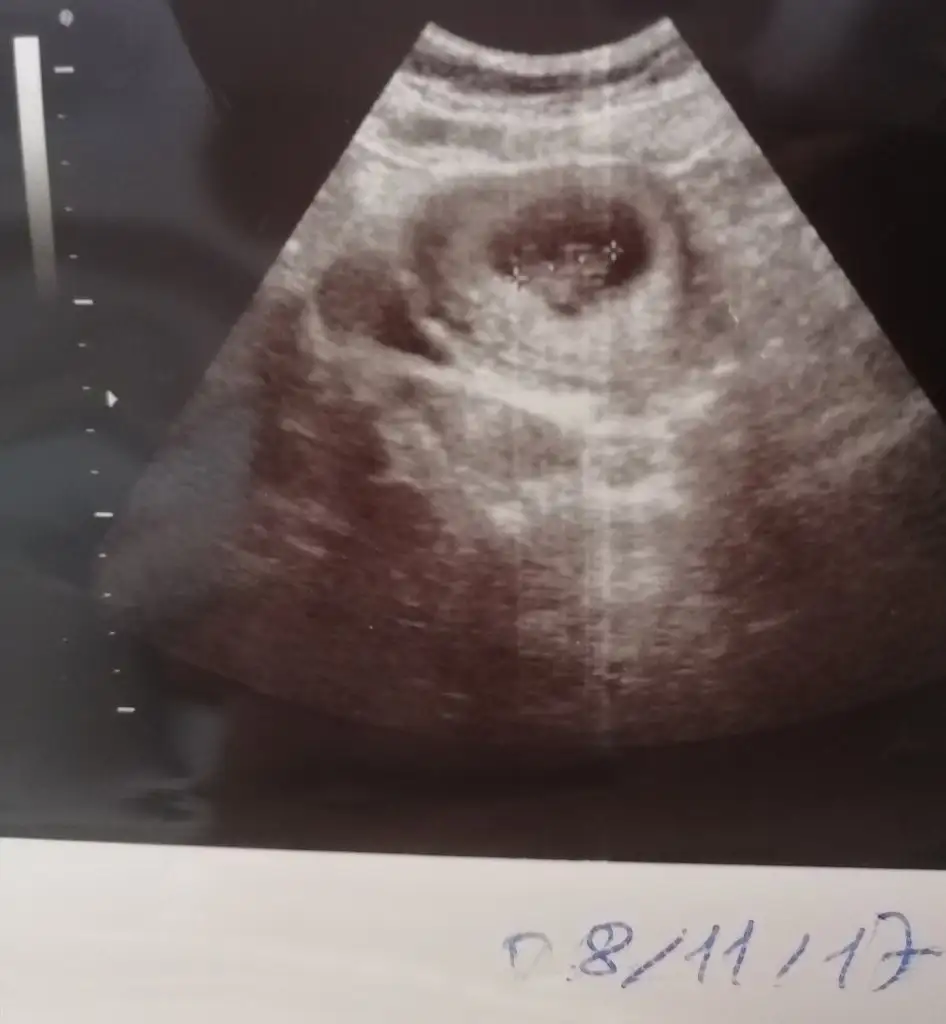

Kızlar kese etrafinda kanama bölgeleri olan var mı? Varsa nelere dikkat ediyorsunuz. Bebeğim USG bir hafta geri de çıkıyor.arayi kapatır mi ?

Kanama bölgem var mı bilmiyorum ama bir kez lekelenme olduğu için progestana başladık, ağır kaldırmak, kendini çok yormak ve ilişki yasak en az üç ay dedi doktorum.